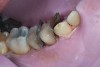

(3.) Preoperative occlusal view of lower arch with orthotic in place.

Figure 3

Ultimately, the patient developed joint and muscle symptoms due to his lack of posterior support and sought the help of a specialist. His bite was analyzed, and he was fitted with a dental orthotic that allowed his teeth to touch in centric relation (Figure 3). This was intended to be a temporary measure to stabilize the patient's bite and make him comfortable, but before any permanent treatment could be carried out, he moved abroad and had been living with the device for more than four years before the time of the consultation. He stated that his bite was now very stable with the orthotic, but he was looking for a more permanent solution and also wanted to improve the overall appearance of his smile.

A comprehensive examination was carried out, and preoperative photographs were taken (Figure 1 through Figure 4). The patient presented with fair oral hygiene and slight, generalized tissue inflammation. Caries and defective restorations were detected on teeth Nos. 4, 5, 13, and 14. The crown on tooth No. 12 was showing signs of leakage, and although the endodontic access cavity had been temporarily restored with composite, this endodontic re-treatment was acceptable and the tooth was otherwise symptom-free. Erosion was present on most of the posterior teeth and the cuspids, and abrasion was noted on teeth Nos. 4, 5, 10, 11, 20, 21, 22, 28, and 29. An examination of the patient's muscles, joints, and bite revealed no joint sounds, a normal range of motion, and negative joint load and immobilization tests.

The patient's removable dental orthotic covered the lower bicuspids and first molars. With the orthotic in place, there was shim stock contact on all posterior teeth and on the second molars that were not covered by the appliance. However, there was no incisal overlap and a lack of anterior guidance.11 When the orthotic was removed, solid shim stock contacts were present on the second molars and the right lateral incisor. These contacts were reproduced every time the appliance was removed. The same contacts were found on the patient's mounted models, which confirmed that the joints were in centric relation. Whether the lower second molars had overerupted as a result of wearing the appliance or had already been in this position before the orthotic was fitted could not be established. Apart from these three contacts, no other teeth touched, and there was a 2-mm space between the posterior teeth, making mastication difficult. Interestingly, wear facets were present on the palatal surfaces of the upper central and lateral incisors, indicating that at some point in time, there had been significant overlap of the anterior teeth and a possible constriction of the chewing envelope. Analysis of a cephalometric radiograph showed a class II growth tendency with a reduced mandibular plane angle, which supported the theory that the patient had at one time possessed a class II occlusion.